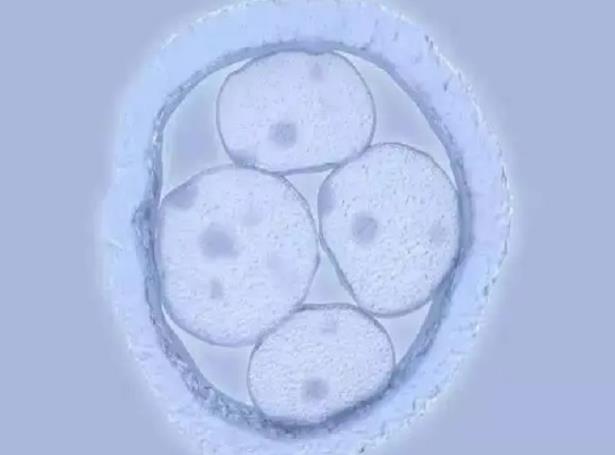

45岁之后,很多女性都处于围绝经期,卵巢内可以利用的卵子很少。同时,随着年龄增加,卵子质量下降,受精后,发生染色体异常分裂的概率大大增加,相应的,染色体异常的胚胎生成增加。数量和质量都下降的情况下,胚胎着床率大大下降,临床妊娠率<5%,接近为0,即使怀孕,出现胚胎停育的风险也大大增加。